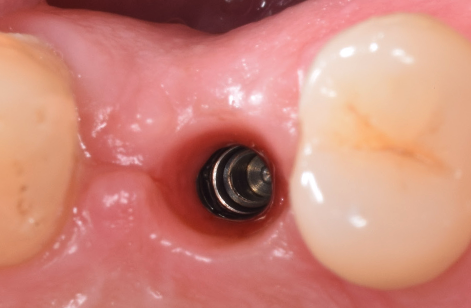

După perioada de osteointegrare a implantului acesta se descoperă, adică se creează o cale de comunicare cu mediul bucal, el până în această etapă fiind acoperit de gingie. Se instalează apoi un bont de vindecare care are rolul să ghideze vindecarea gingiei în jurul implantului.(Fig. 3.5.5 și 3.5.6) Cu acest bont pacientul așteaptă o perioadă variabilă de 14-21 de zile, iar dacă după acest interval gingia este vindecată, se poate trece la etapa următoare – cea de amprentare.